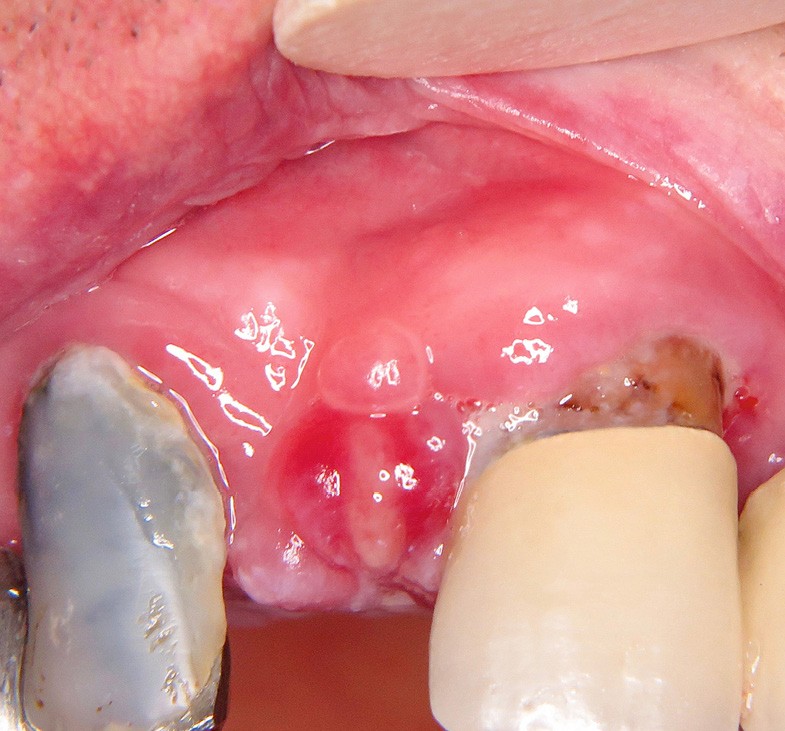

4. Épulis postextractionnel

- Granulome intra-alvéolaire à la suite d’une avulsion dentaire (fig. 4a et b).

- Absence de cicatrisation spontanée.